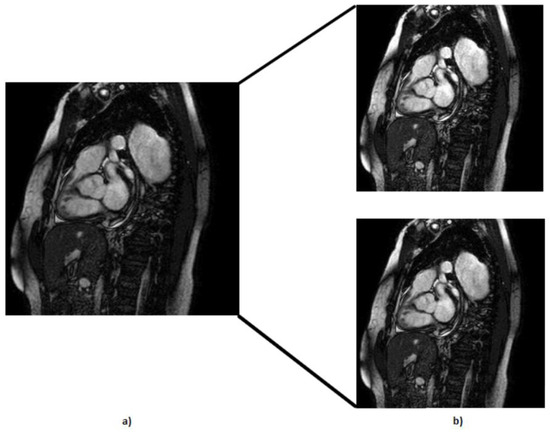

- We executed translation along the x-axis (Figure 5) while meticulously ensuring that the aortic valve remained within the frame; with this, we created 202 more MRIs out of the original dataset.